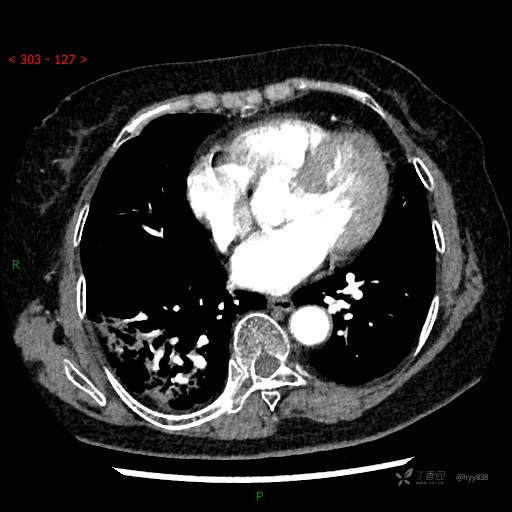

静脉期